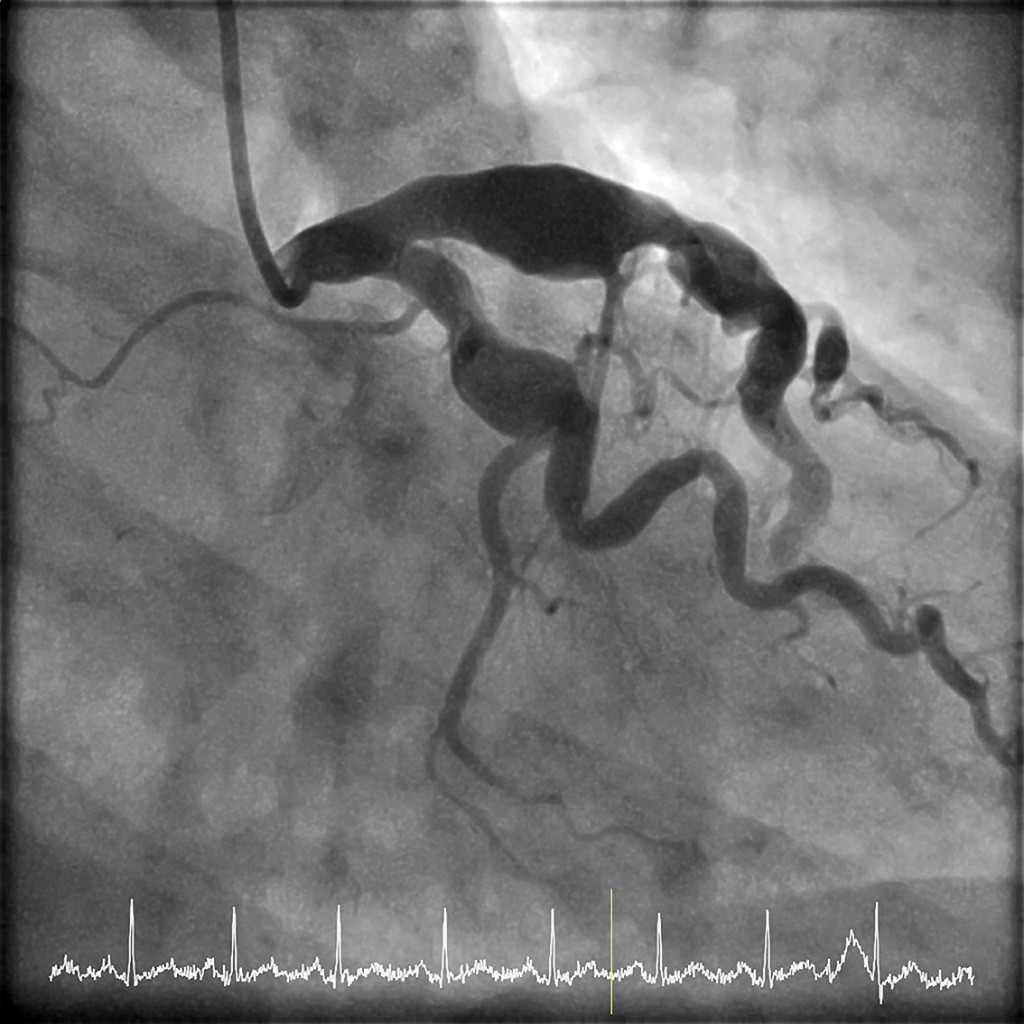

Koronar angiografi viser fusiforme aneurismer i venstre koronararterie med diameter opptil 13 mm. Pasienten hadde også en akutt okklusjon i et tilsvarende aneurisme proksimalt i høyre koronararterie (se video).

Under den aktuelle innleggelsen viste koronar angiografi progrediering av aneurismene. Påfølgende morgen ble pasienten akutt dårlig med brystsmerter og hypotensjon, og EKG viste ST-elevasjon i nedre vegg. Ny koronar angiografi viste oppstått okklusjon av høyre koronararterie. Det ble utført trombeaspirasjon og ballongdilatasjon med gjenopprettelse av blodstrøm, men med tegn til distal embolisering. Adjuvant antitrombotisk behandling med blodplateaggregasjonshemmeren eptifibatid ble gitt i 24 timer.